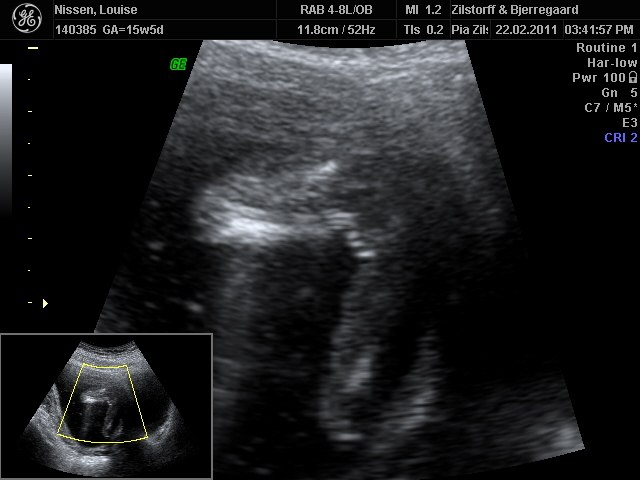

Vi har været til kønsscanning og er i uge 15+5...

Hvad er jeres gæt på hvad vi får?

Vedhæftede fotos (klik for at se i fuld størrelse)

Jeg kan slet ikke se hvad det er på den scanning, desværre.... så det kan jeg ikke give noget gæt på

det er da en bette prinsesse tillykke med det!

piige

prinsesse

en pige  fint at du er ano, men er det ik dit navn der står på billedet?

vil også sige en bette pige.

Ha ha jo, men skriver ano for på min profil står der nemlig alt lillepigen   dejlig i ku se det for er kommet helt i tvivl efter en gammel læge sagde idag, ja ja nu skal man ik tror på de kønsscanninger der...